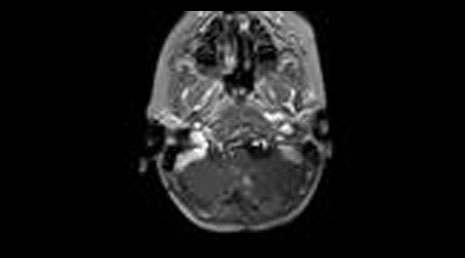

40. Mesial temporal sclerosis- temporal lobe epilepsy